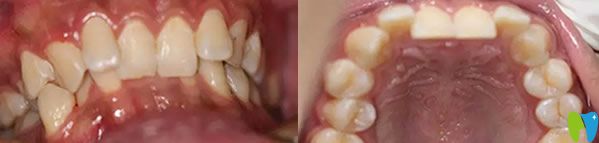

福州登特口腔牙齒矯正前后效果對比圖:

登特口腔牙齒矯正前后效果對比圖

這就是我在福州登特口腔做的金屬托槽牙齒矯正14個(gè)月恢復(fù)效果圖,終于解決了我牙齒擁擠不齊的困擾,達(dá)到了預(yù)期的治療效果,恢復(fù)了牙齒的咀嚼功能。而且經(jīng)濟(jì)實(shí)惠整個(gè)診療過程花了12000元左右,大家覺得我在福州登特口腔矯正牙齒的價(jià)格貴嗎?